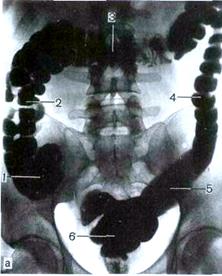

Рис. 302270650. Рентгенограмма толстой кишки через 48 часов после приёма контрастной массы per os.[43]

Водную бариевую взвесь вводят через задний проход с помощью аппарата Боброва в количестве 600—800 мл. Оценивают положение, форму, величину, очертания, смещаемость всех отделов толстой и прямой кишки (рис.302270945). [48]

Рис.302270945. Рентгенограммы толстой кишки после ретроградного заполнения контрастным веществом: 1 — слепая кишка, 2 — восходящая ободочная, 3 — поперечная ободочная, 4 — нисходящая ободочная, 5 — сигмовидная ободочная, 6 — прямая. [49]